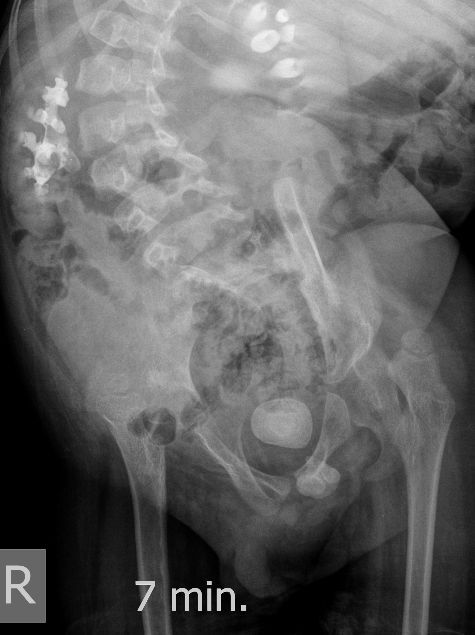

Для того, чтобы продемонстрировать степень ортопедических проблем и облегчить задание (или усложнить :) ) добавляю обзорную рентгенограмму брюшной полости

DX0001.jpg

Нейрогенный мочевой пузырь (?), МКБ, конкремент мочевого пузыря, двухсторонний мегауретер, конкремент правой почки.

И что законтрастировалось на экскреторных урограммах около мочевого пузыря?

DX0004.jpg

Плохо разбираюсь в Рг-исследованиях.

Стриктура уретры с расширением ее проксимального отдела?

Если честно, и я изначально не совсем понял, где находится конкремент (а это конечно же конкремент), локализованный на урограммах. При первичном исследовании на УЗИ его я не видел (либо он спрятался за тенью конкремента мочевого пузыря, либо я обрадовался редкой находке конкремента такого размера в мочевом пузыре - 2.5 см, и не посмотрел что ниже). Тем не менее при ретроспективном анализе архивированных сонограмм, как мне кажется, он попал в один из сканов, м.б. не совсем чётко.

И всё -же, где конкремент :?:

Возможно, в дивертикуле либо в нижней трети мочеточника..